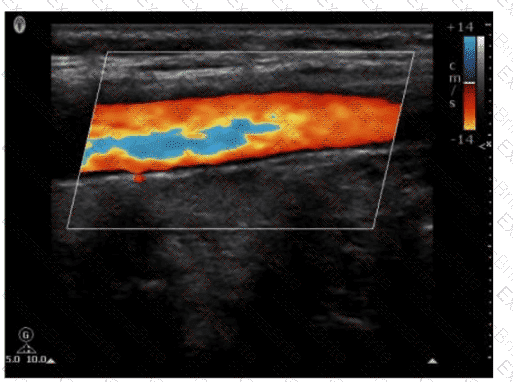

Which adjustment resulted in the change from image A to image B?

Options:

A.

Increased transmit frequency

B.

Increased scale

C.

Decreased color gain

D.

Decreased acoustic power